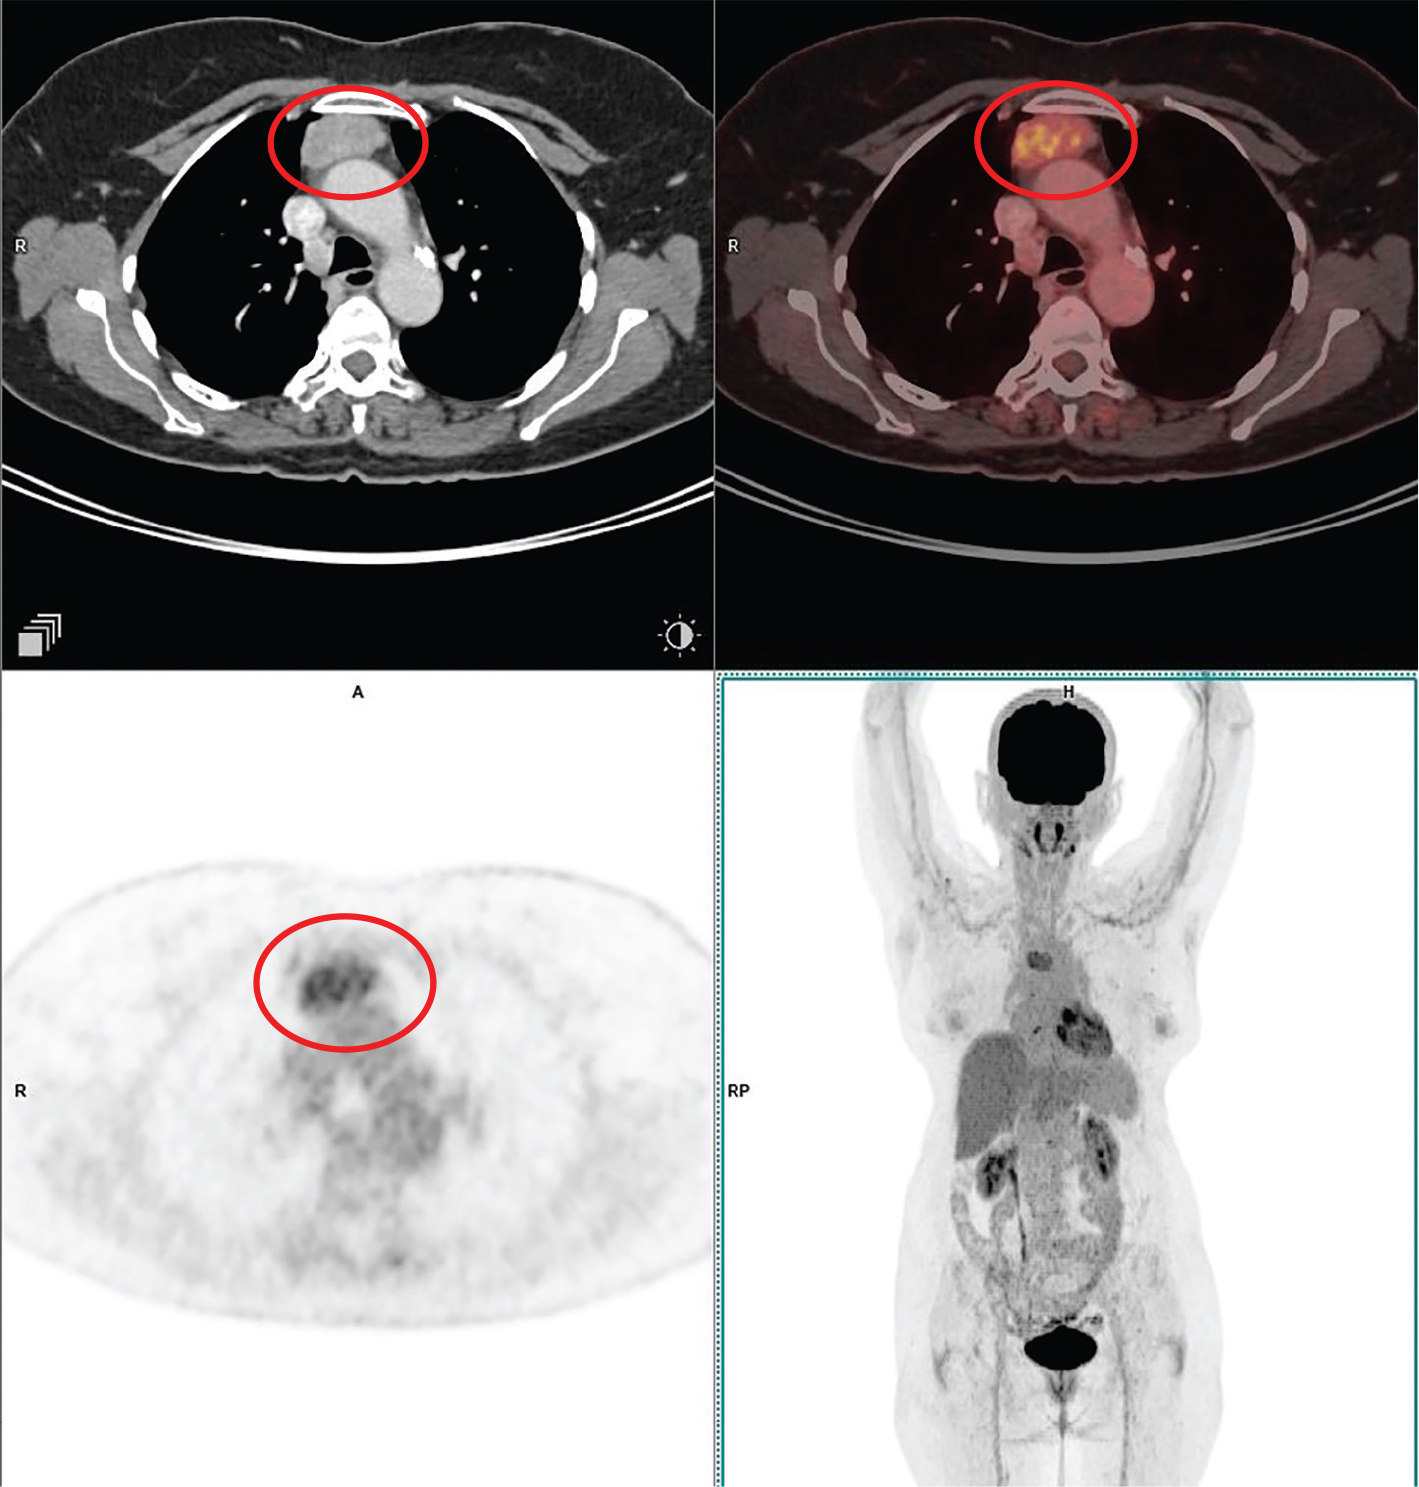

18F-FDG PET/CT in patients with HL and high-grade or aggressive non-Hodgkin lymphoma (NHL) consistently has very high sensitivity (63). 18F-FDG PET/CT improved the characterization of lesions that were uncertain on other types of imaging and often detected nodal and extranodal disease sites that were missed by conventional staging techniques. An example of 18F-FDG PET/CT showing synchronous sites of supra and infradiaphragmatic involvement is seen in Figure 4.

Fig 4

Figure 4. Diffuse large B cell lymphoma. Anterior mediastinal mass that was pathologically confirmed as NHL (Diffuse large B cell lymphoma). FDG PET/CT images include axial CT (top left panel), fused axial PET/CT (top right panel), axial PET (bottom left panel), and maximum intensity projection (MIP) PET image (bottom right panel). In the red circle, an enhancing lobulated intensely FDG avid soft tissue mass is seen in the anterior mediastinum on right side of midline, extending into the middle mediastinum. The lesion shows broad based abutment with the mediastinal pleura and compresses the SVC with resultant luminal narrowing. There was additional FDG avid heterogeneously enhancing lesion in the junction of head and neck of pancreas (not on the included PET/CT images and could be appreciated on the MIP image) that were suggestive of synchronous lymphomatous disease involvement.

The results of 18F-FDG PET/CT, which are used during and after treatment for HL and aggressive NHL, have a high prognostic value and correlate with survival. Updated response criteria for aggressive lymphomas now include 18F-FDG PET/CT. Figure 5 shows the impact of the interim response assessment with 18F-FDG PET/CT by demonstrating the minimal persistent residual metabolically active disease (with Deauville score 4) which would have been interpreted by conventional anatomic imaging modalities as post-treatment fibrotic residue.

Fig 5

Figure 5. Staging and interim response assessment 18F-FDG PET/CT scans. 18F-FDG PET/CT images include fused axial PET/CT of the patient taken during staging on the left column and interim response assessment after 3 cycles of chemotherapy on the right column (comparative lesions marked with small white arrows). First row showing complete resolution of the bulky component of the disease. Second row showing persistent minimal metabolically active residual disease (Deauville’s score 4) abutting the pericardium and third row showing complete resolution of the pancreatic lesion and adjoining peripancreatic lymph node.